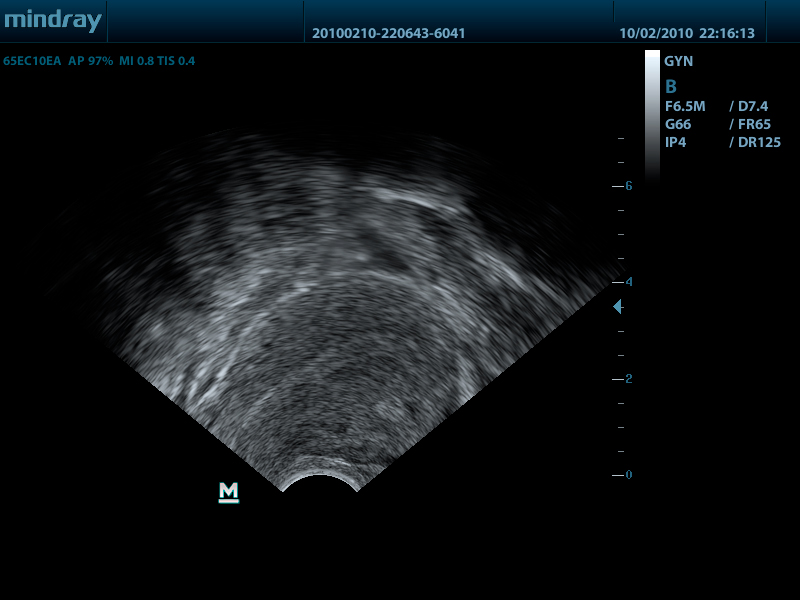

Внутриполостной датчик 65EC10EA (5.0/6.5/7.5/8.5/Н8.0/Н9.0 МГц, R-10 )

Mindray DP-50 – портативная цифровая ультразвуковая система с ЖК монитором 15 дюймов (1024Х768)

- диапазон сканируемых частот от 2,0 до 14,0 МГц

DP-50 – портативный УЗИ сканер разработан на базе новой платформы X-treme engine, используемой в хорошо зарекомендовавших себя цветных сканерах с доплером моделей DC-3, DC-7, DC-6. Эта платформа открывает возможности для расширений до уровня цветных сканеров и совместимости с широким диапазоном периферийного оборудования. X-treme означает интеллект, высокую скорость обработки данных, многоуровневую передачу сигналов, а также возможность оптимизации изображения и модульного расширения.